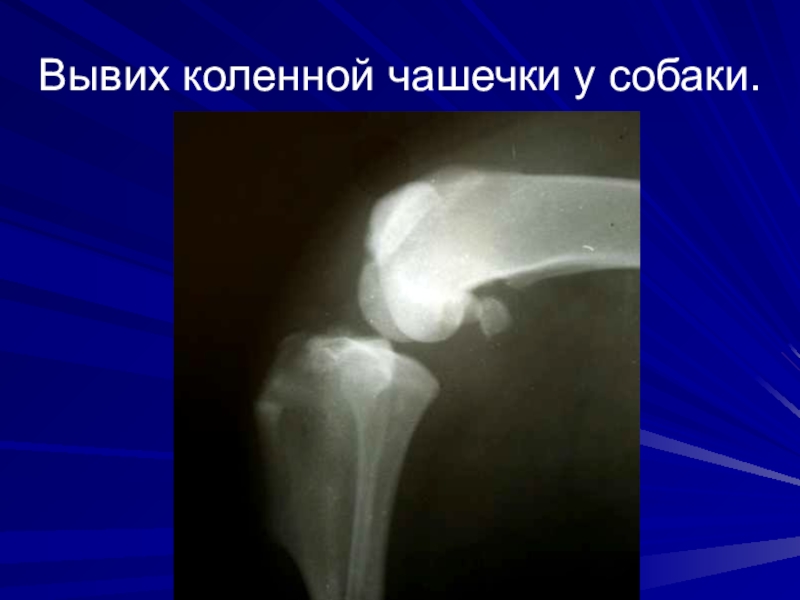

Слайд 18Вывих коленной чашечки у собаки.

Вывих коленной чашечки у собаки.